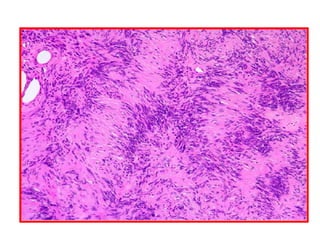

34- Leiomyoma

1           Rheumatic Myocarditis

2

3

1) Myocardium

2) Blood vessels

3) Perivascular Aschoff body

Rheumatic Myocarditis

1

1) Fibrinoid degeneration of collagen fibers and interstitial edema

2) Aschoff giant cell